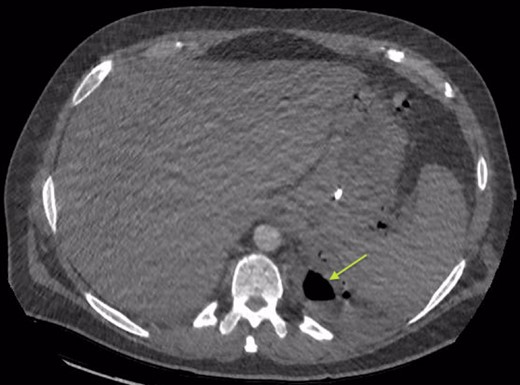

Chest X-ray in ICU following drainage showed what was thought to be Pneumomediastinum (Figs 1 and 2), and given this concern he was referred to the Cardiothoracic service. Subsequent CT suggested a large loculated hydro-pneumothorax, which in retrospect represented the drained Pseudocyst communicating through the diaphragm (Figs 3 and 4).

Area of communication between the drained Pseudocyst and the Left Pleura. Space noted with arrow.